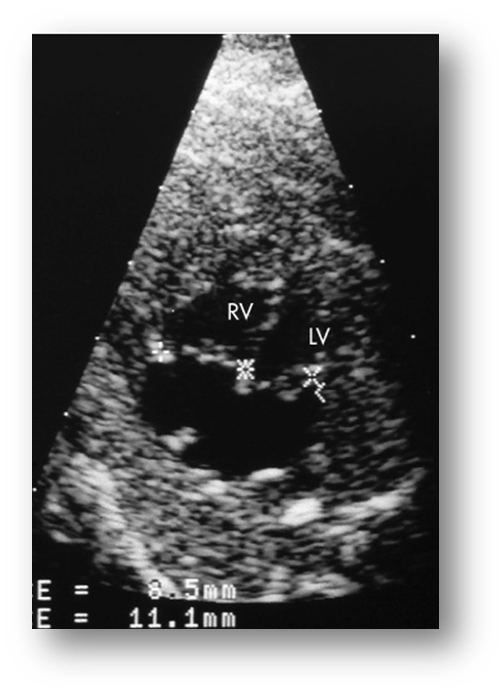

____ chamber view compares placement of mitral valve with slightly apical position of tricuspid valve.

4 [LVOT view may be used too]

Check for mobility of leaflets

Mitral Stenosis